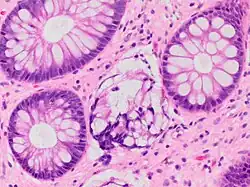

| A micrograph demonstrating cryptitis, a microscopic correlate of colitis. H&E stain. | |

An important investigation in the assessment of colitis is biopsy for histopathology. A very small piece of tissue (usually about 2mm) is removed from the bowel mucosa during endoscopy and examined under the microscope by a histopathologist. A biopsy report generally does not state the diagnosis, but should state any presence of chronic colitis, give an indication of disease activity, as well as state the presence of any epithelial damage (erosions and ulcerations).[6]

Histopathology findings generally associated with chronic colitis include:[6]

-

Crypt degeneration -

Crypt branching and other architectural distortions -

Paneth cell (pictured) or gastric metaplasia (only applies in the left colon and rectum)

Other findings include basal plasmacytosis and mucin depletion.[6] Histopathology findings generally associated with active colitis include:[6]

Neutrophilic cryptitis (neutrophils within crypt epithelium) -

Crypt abscesses (luminal neutrophilic aggregates) -

Gland destruction -

Ulceration (seen here as absence of epithelium, and granulation tissue with many fibroblasts)